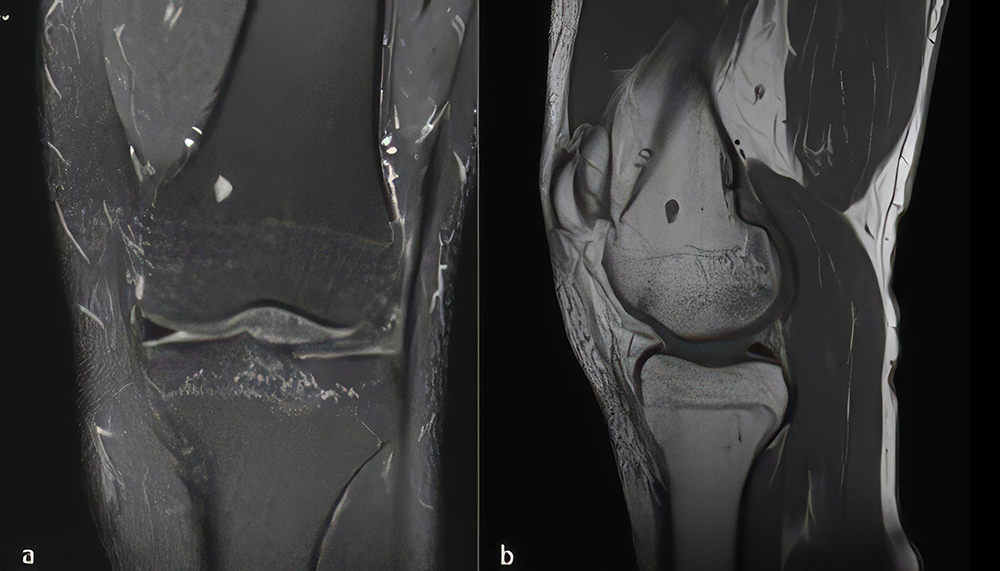

Figure 1. . Image of a 34-year-old patient with an approximately 7 mm endchondroma lesion in the distal metaphysis of the femur. a) Coronal sections show a hyperintense lesion on intraosseous proton fat-suppressed sequences. b) Sagittal sections show a hypointense lesion on T1A-weighted images